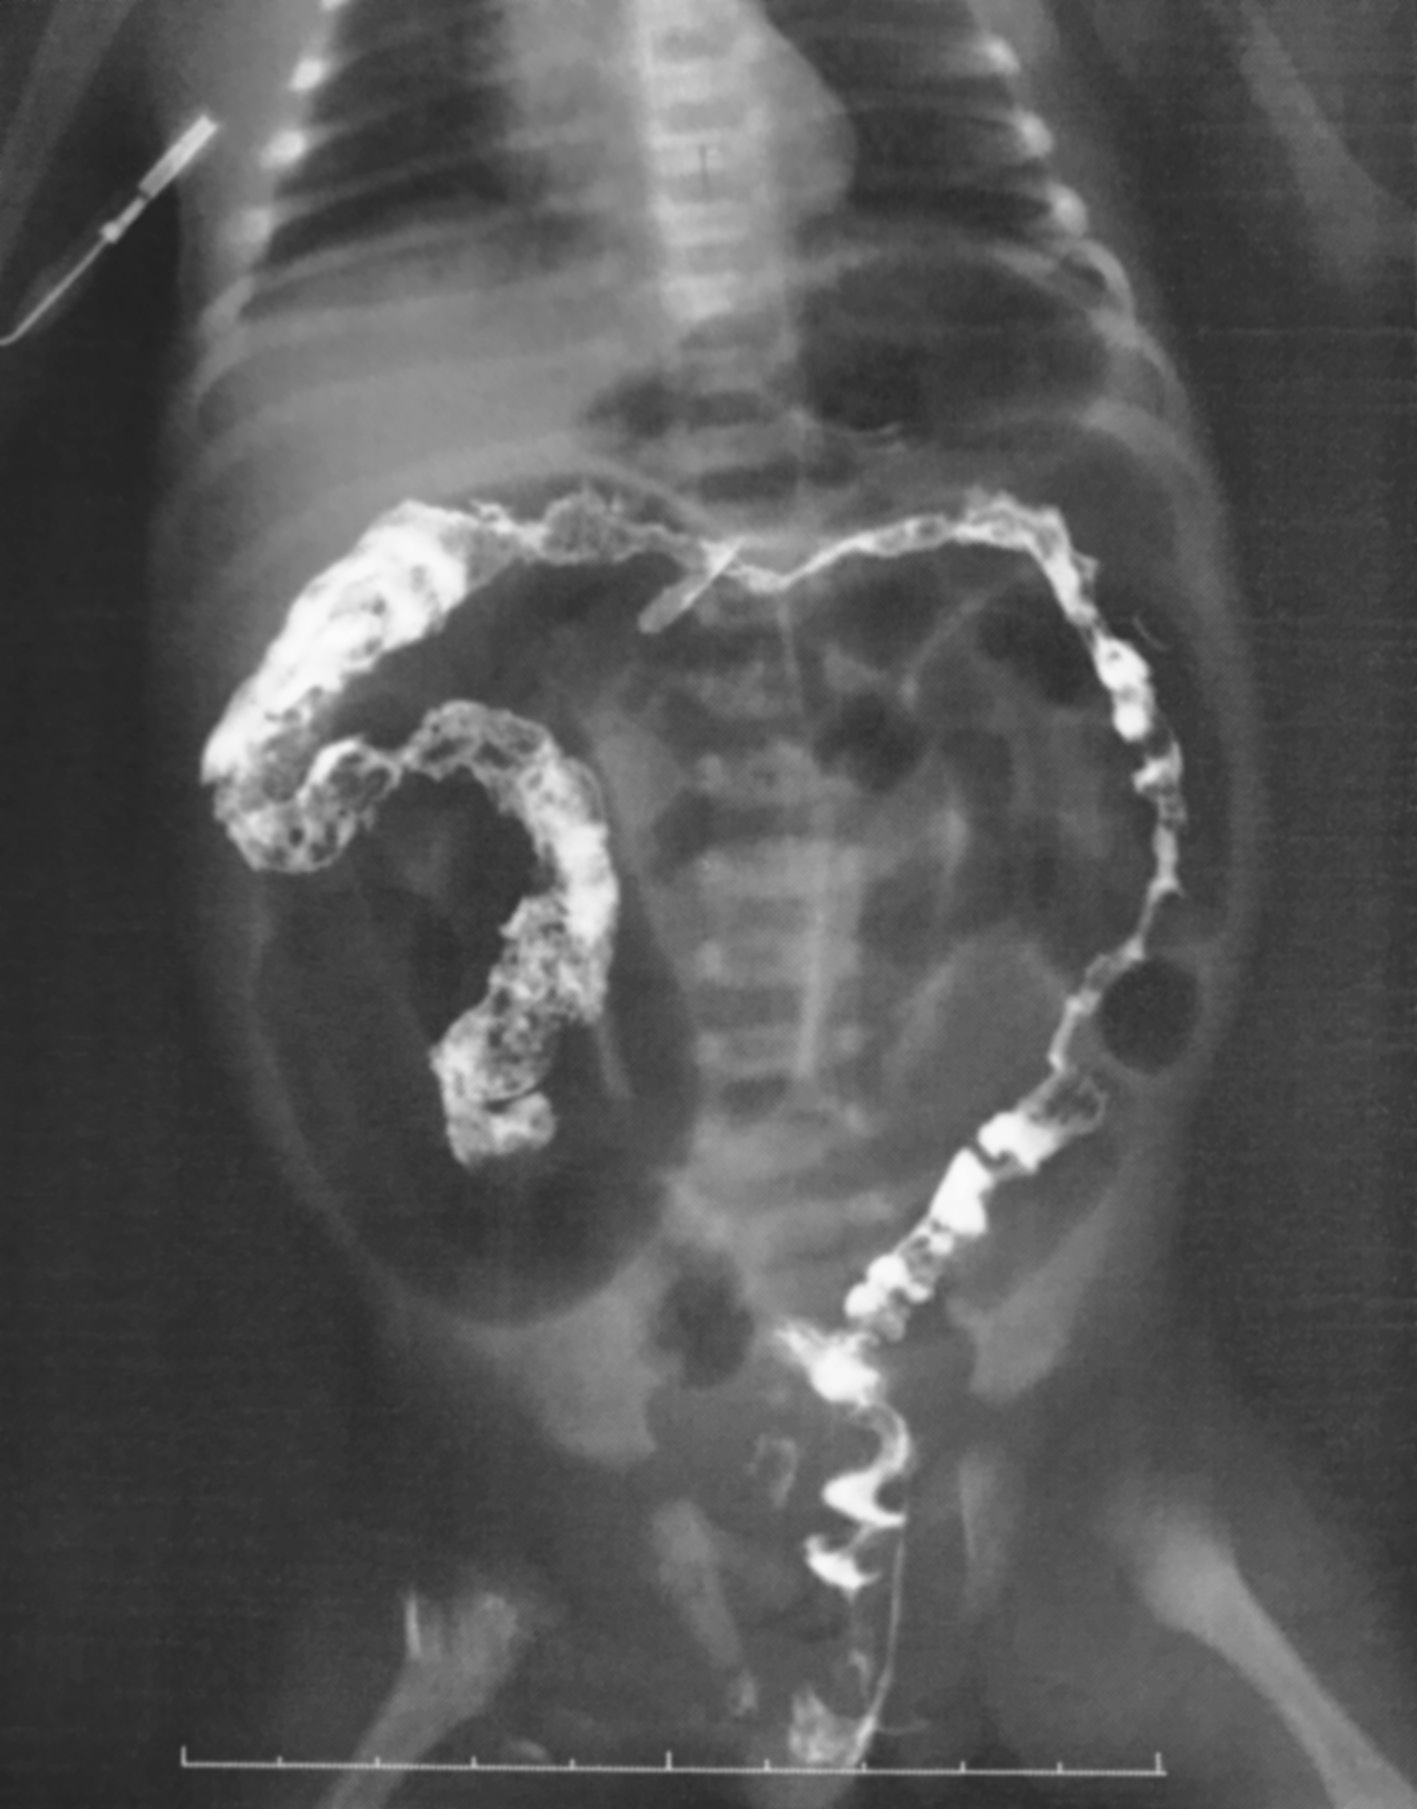

结肠钡剂灌肠检查可以清晰地显示出病变肠管的部位及累及范围。HD病变肠段肠壁无正常蠕动,无张力,僵直,肠黏膜光滑,肠管如筒状。典型的狭窄段、扩张段及移行段的显示是最具特征性的X线表现,是明确诊断及分型的依据,其准确率达80%左右。狭窄段、扩张段及移行段的特点:狭窄段肠管宽度均在正常值以下,连续观察此段肠管走行僵硬,无法正常扩张;移行段位于狭窄段及扩张段肠管之间,多呈漏斗状或环形狭窄;扩张段位于移行段以上,肠管明显扩张。钡剂灌肠后24小时及48小时摄片可进一步评估钡剂的残留情况,了解动力障碍肠管病变的范围,亦为手术切除方式提供依据。

不同类型的HD钡剂灌肠检查的表现亦不同,见图3-3~图3-9。

图3-6 长段型先天性巨结肠症钡剂灌肠

狭窄段累及直肠、乙状结肠及降结肠。